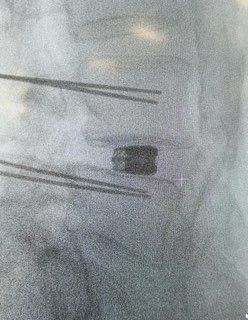

Starszy Asystent w Klinicznym Oddziale Neurochirurgicznym oraz Poradni Neurochirurgii Wojewódzkiego Szpitala Specjalistycznego im. św. Barbary nr 5 w Sosnowcu. Konsultant Kliniki Neurologii Szpitala Klinicznego nr 1 w Zabrzu. Absolwent Wydziału Lekarskiego Śląskiego Uniwersytetu Medycznego w Zabrzu. Staż podyplomowy odbył w latach 2010-2011 w Oddziale Neurochirurgii WSS nr 4 w Bytomiu. W 2018r. złożył egzamin specjalizacyjny po zakończeniu szkolenia w ramach rezydentury w WCM Opole. W 2019 roku uzyskał stopień doktora nauk medycznych. Specjalizuje się w kompleksowym leczeniu schorzeń kręgosłupa (dyskopatia, stenoza kanału kręgowego, kręgozmyk) oraz neuroonkologii. Szczególny zakres działań medycznych to nowoczesne, małoinwazyjne operacje kręgosłupa z wykorzystaniem technik endoskopowych (mikrodiscektomia - implanty rozprężalne), przezskórnych stabilizacji oraz mikrochirurgicznych dekompresji. Wykonuje procedury iniekcyjne; discoGEL, GelSTIX, kriolezje oraz blokady przeciwbólowe kręgosłupa odcinka szyjnego, lędźwiowo-krzyżowego a także stawów krzyżowo-biodrowych, które odgrywają istotną rolę w procesie diagnostyczno-leczniczym wielu zespołów bólowych. Na co dzień przeprowadza operacje w ramach kontraktu z NFZ. Członek Polskiego Towarzystwa Neurochirurgów oraz Polskiego Towarzystwa Chirurgii Kręgosłupa. Uczestnik wielu krajowych i zagranicznych kursów neurochirurgicznych, m.in. w Czechach, Słowacji, Niemczech, Włoszech, Danii, Austrii, Szwajcarii i USA. Autor licznych publikacji naukowych.

Zdjęcia i filmy